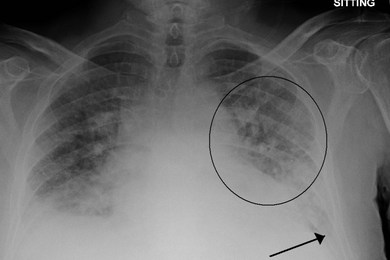

Scientists employ an underused resource — radiology reports that accompany medical images — to improve the interpretive abilities of machine learning algorithms.